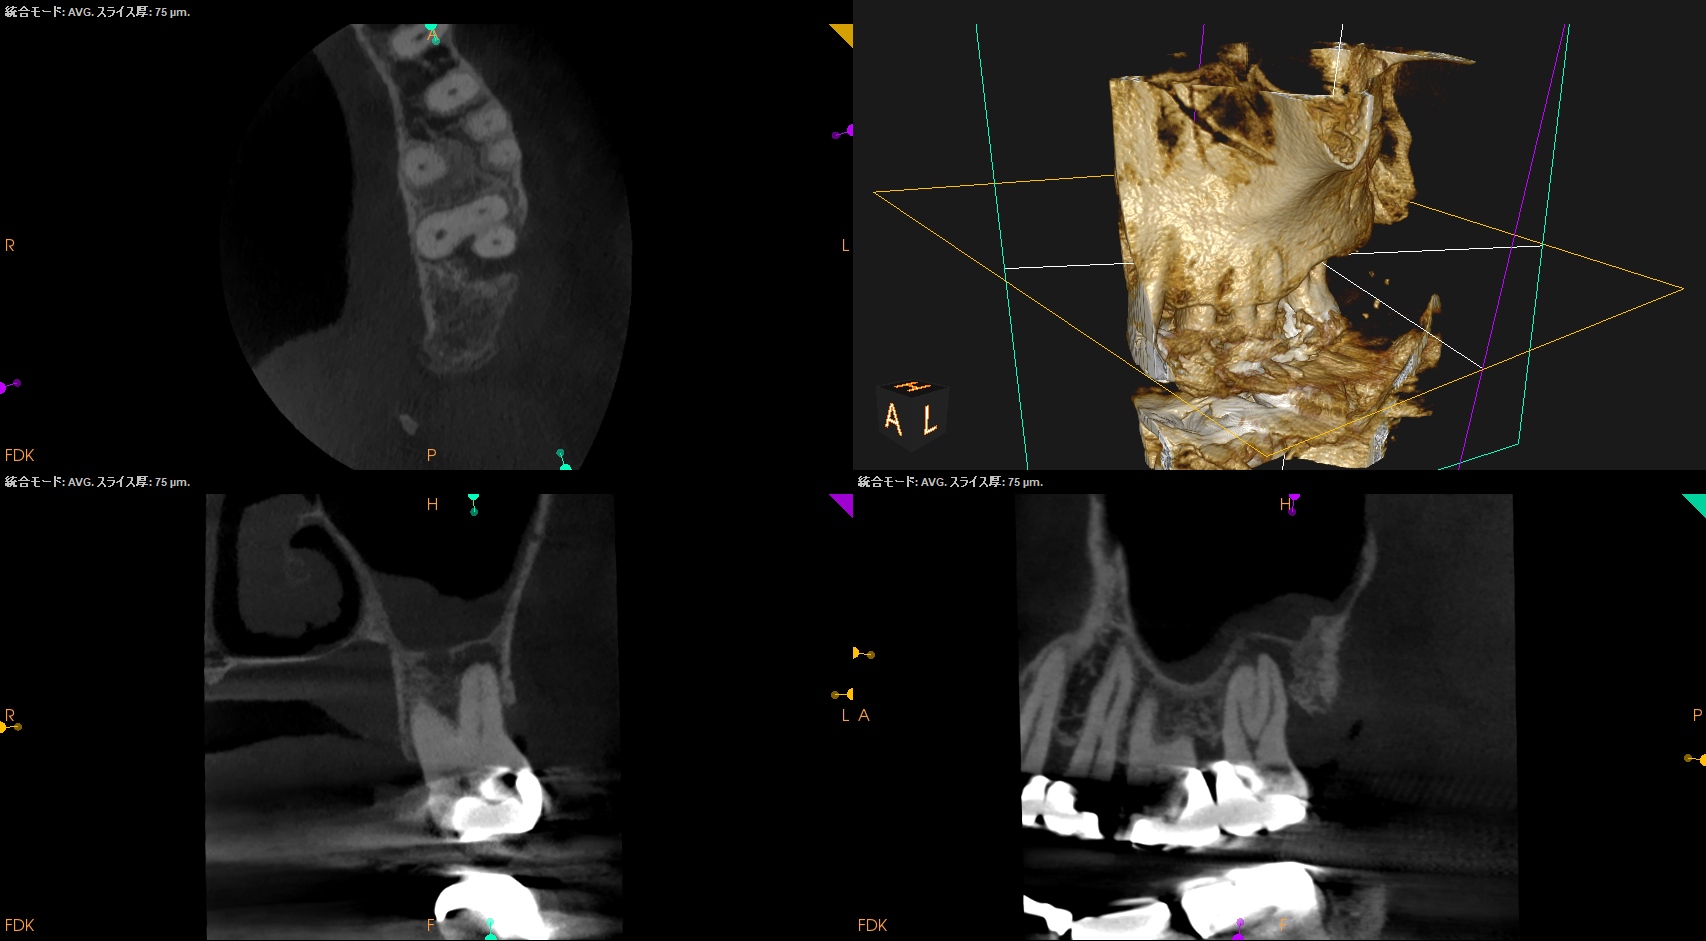

#15 RCT 1yr recall(2025.10.28)

MB

DB

P

初診時と比較した。

根尖病変、

術前の臨床症状、

術前の歯周ポケット

は完治した。

最終補綴もOKだ。

この日で経過観察も終診とさせていただいた。

長い間、お疲れ様でした。